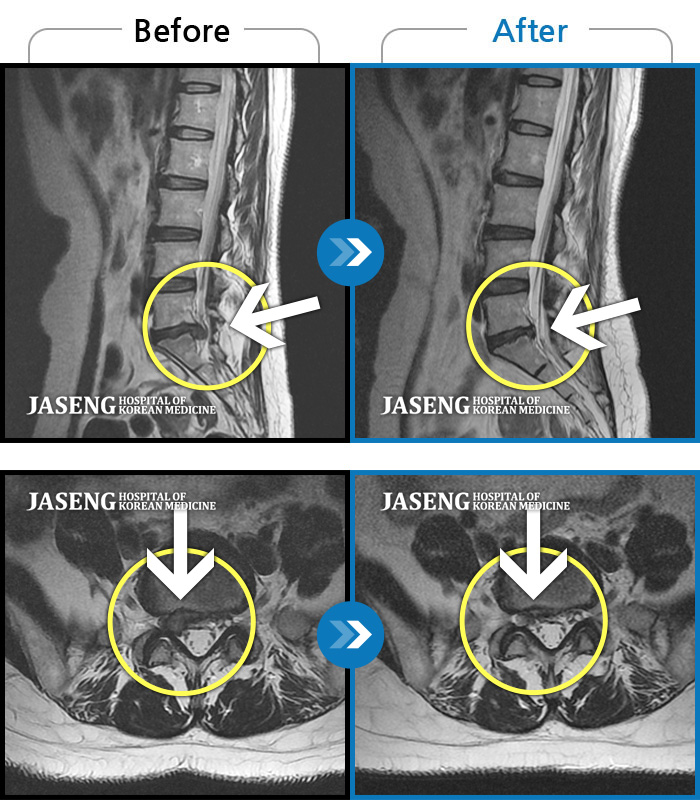

Before

After

환자에게 사전 동의를 받아 동일 조건에서 촬영되었습니다.

개인에 따라 치료 후 부작용이 발생할 수 있으니 의료진과 상담 후 치료를 진행하시기 바랍니다.

허리통증, 골반 저림, 발가락 근력저하가 심하여 일상생활이 불가능한 상태